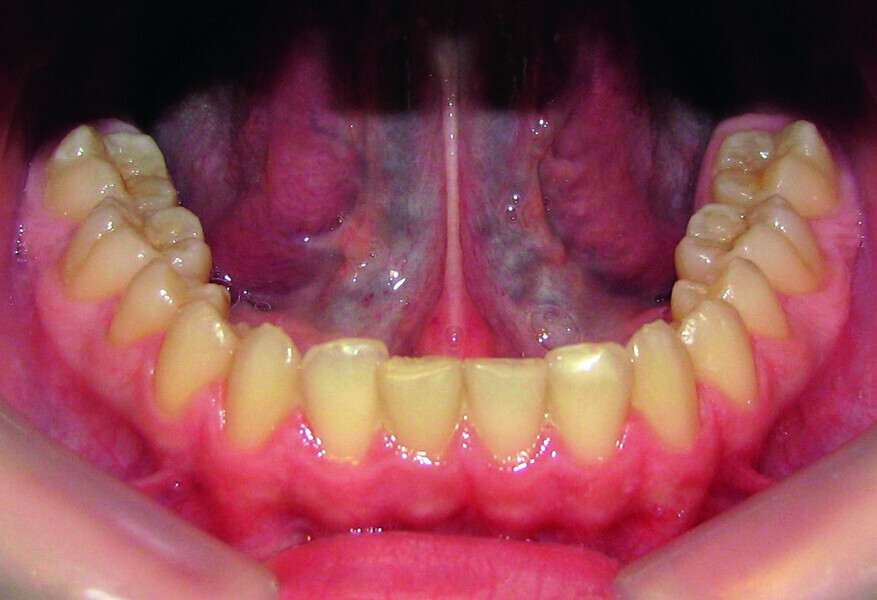

Orthodontic management of maxillary lateral incisors agenesis